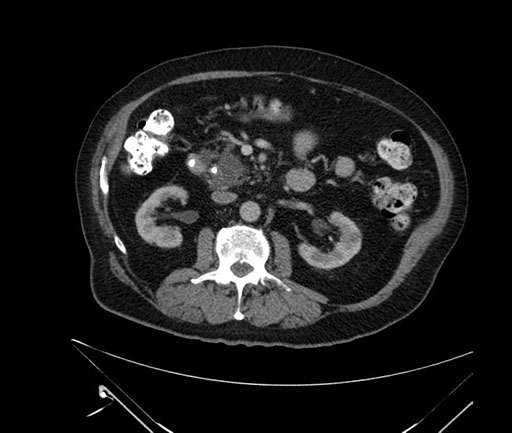

Whipple (pancreaticoduodenectomy) [case 7]

Imaging Analysis

Look through the patient's CT scan to identify any areas of concern for the necessary procedure.

Based on your CT findings, which issue(s) would give reason for "planned slowing down moment(s)" in this case?

Considering a standard Whipple procedure, what step(s) of the operation would you do differently in this case?